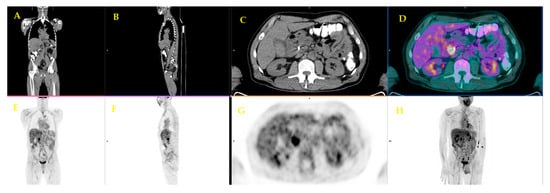

| 16 | Ghaneh et al. [31] | 2018 | Prospective study | 589 | Whole management | FDG PET/CT, in addition to standard diagnostic work-up of PDAC, correctly changed the staging of PDAC in 10% of cases, influenced the planned management in 45%, avoided un-useful resection in 20% of patients scheduled for surgery, and got a limited role in chronic pancreatitis. |